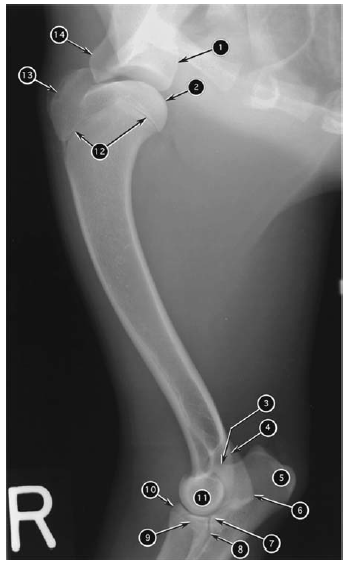

Mediolateral radiograph of canine humerus

What number?

- Greater tubercle of humerus

- Proximal physis of humerus

- Head of humerus

- Condyle of humerus

- Lateral epicondyle of humerus

- Medial epicondyle of humerus

- Anconeal process of ulna

- Lateral coronoid process of ulna

- Medial coronoid process of ulna

- Tuber olecrani

- Head of radius

- Proximal radioulnar joint

- Infraglenoid tubercle of scapula

- Supraglenoid tubercle of scapula

A

1. Infraglenoid tubercle of scapula

2. Head of humerus

3. Anconeal process of ulna

4. Lateral epicondyle of humerus

5. Tuber olecrani

6. Medial epicondyle of humerus

7. Lateral coronoid process of ulna

8. Proximal radioulnar joint

9. Medial coronoid process of ulna

10. Head of radius

11. Condyle of humerus

12. Proximal physis of humerus

13. Greater tubercle of humerus

14. Supraglenoid tubercle of scapula